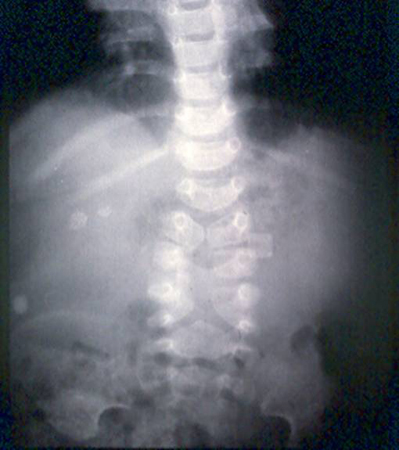

Radiografia abdominal de neonato com padrão fecal anormal e constipação. Os cólons transverso e descendente dilatados são sugestivos de doença de Hirschsprung

Do acervo de Dr. KuoJen Tsao; usado com permissão